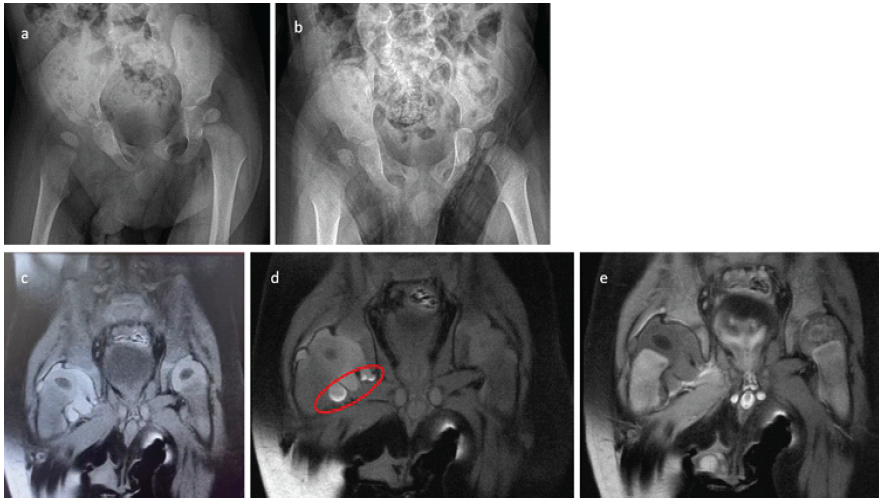

A 6-month-old, otherwise healthy boy was admitted to the pediatrics clinic of an external hospital with unexplained pain and irritability. During the physical examination, the patient demonstrated signs of agitation and distress, particularly with movement of the right hip, which exhibited a restricted range of motion. Notably, no signs of hyperemia or warmth were present upon palpation of the right hip, and the remainder of the physical examination was unremarkable. The parents reported that the infant’s restlessness began 1 day before the visit. Medical history revealed no significant findings. A full-body magnetic resonance imaging (MRI) had performed to identify the potential source of the pain, revealing an effusion in the right hip (Fig. 1c, d, e). The patient was referred to a Level I training and research hospital with a provisional diagnosis of septic arthritis.

Figure 1: (a) Pre-operative X-ray showing subluxation of the right hip due to effusion. (b) Anteroposterior X-ray taken 12 h post-operatively showing relative relaxation of the right hip compared to the previous day. (c) T1-weighted, coronal fat-saturated magnetic resonance imaging (MRI) revealing a hyperintense effusion in the right hip. (d) T1-weighted, coronal fat-saturated MRI showing blood elements settled in the inferior part of the joint capsule (red circle). (e) T2-weighted, coronal fat-saturated MRI showing hypointense effusion in the right hip, indicative of a blood signal. Both femoral head ossification centers and epiphyses display normal signals, ruling out potential avascular necrosis.